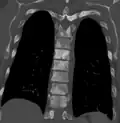

Sclerosis of the bones of the thoracic spine due to prostate cancer metastases (CT image)

Sclerosis of the bones of the thoracic spine due to prostate cancer metastases (CT image) -

Sclerosis of the bones of the thoracic spine due to prostate cancer metastases (CT image)

Sclerosis of the bones of the thoracic spine due to prostate cancer metastases (CT image)